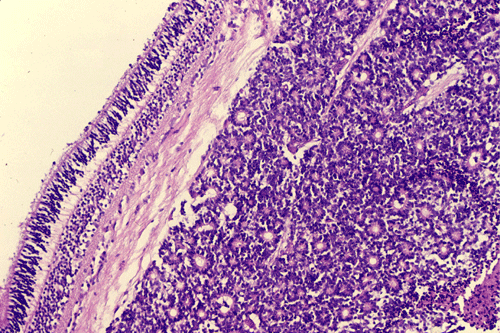

On the whole mount of the globe, there is an exophytic neoplasm that occupies about one-third the volume of the vitreous. The surface of the retina is free of tumor deposition (Panel A). The retina is detached by the mass. There are some pink, necrotic material at the core of the tumor (Panel B). On medium and high-magnification, the tumor is composed of densely packed small cells with hyperchromatic nuclei  without prominent nucleoli. A large number of the cells arrange in rossettes with a well-defined luminal border (Flexner-Wintersteiner rossettes) (Panel C and D). The tumor is confined within the globe and the optic nerve is free from invasion.

Most often, tumor cells arrange in Flexner-Wintersteiner rosettes typified by tall cuboidal cells formaing a small, circumstribed lumen with well defined limiting membrane on the luminal side. The tumor nuclei are found at the basal end of the cuboidal cells while the apical end contains the cytoplasm. Small projections are protruding from the luminal surface into the lumen and these projections represent residual features of photoreceptor cells. Homer-Wright rosettes can also be found but are less common. In between the rosettes are solid sheets of poorly differentiated tumor cells.